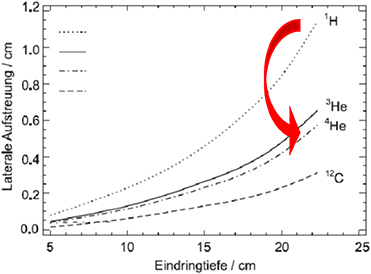

For protons and 3He/4He similar radio-biological properties have been determined, but the lateral scattering is reduced by nearly 50% in the case of helium ions versus protons (figure 5.7). In recent years, helium ions again became of interest for clinical cases where neither protons nor carbon ions are ideally suited, especially for treating paediatric tumours. Currently, patient irradiations with scanned 4He ions at the Heidelberg Ion beam Therapy Center (HIT) in Germany are used only in 'treatment attempts' ('individuelle Heilversuche') and will go into regular operation by mid 2024. Other ion therapy facilities in Europe (e.g., CNAO in Italy and MedAustron in Austria) have also started technical upgrades to produce helium ion beams in the near future.

Figure 5.7. Lateral scattering of different light ions, adapted from Fiedler (2008).

Standard image High-resolution imageRecent studies have shown that 3He ions can be a viable alternative to 4He, as they can produce comparable dose profiles, demanding slightly higher kinetic energy per nucleon, but less total kinetic energy. This results in 20% less magnetic rigidity needed for the same penetration depth which may be of importance for the design of future compact therapy accelerators like superconducting synchrotrons or energy-variable cyclotrons.